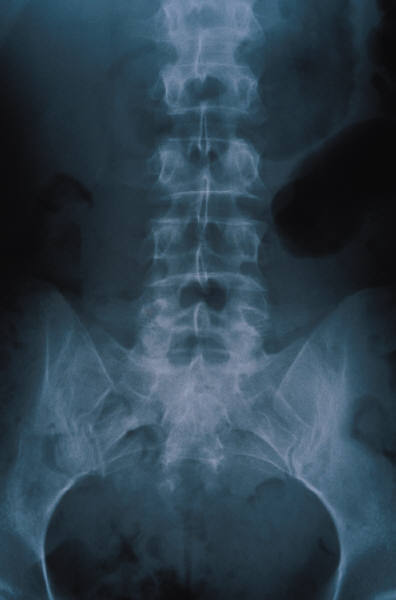

Our office medical assistants are skilled at drawing blood from patients of all ages.  We have an on-site office lab with rapid turnaround and accurate assessment of organ function studies and serologies (disease specific antibodies).  We prefer to review all X-rays and other relavent imaging ourselves and thus can recognize specific features of various disease states allowing more accurate diagnosis and prognosis.